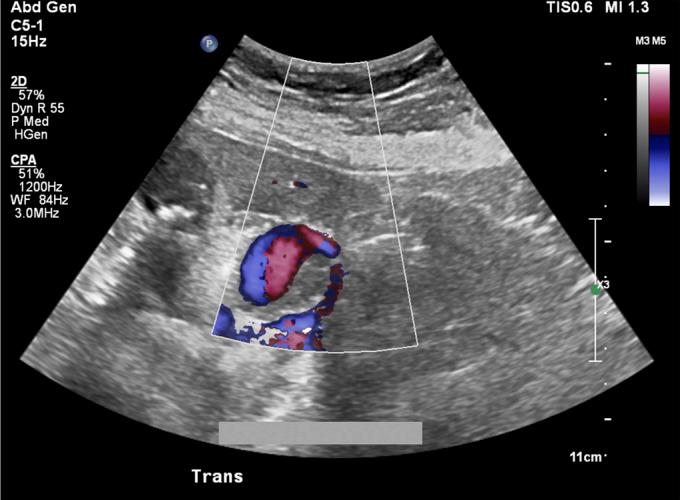

成功微创治疗导致肝外胆管受压的胃十二指肠动脉假性动脉瘤

Successful Minimally Invasive Management of a Gastroduodenal Artery Pseudoaneurysm Causing Extrinsic Bile Duct Compression.

Gastroduodenal artery (GDA) pseudoaneurysms are rare clinical entities that typically develop in the setting of chronic inflammation of the pancreas, although idiopathic pseudoaneurysms can occur. Although GDA pseudoaneurysms carry the risk of rupture with resultant hemorrhage, they seldom are reported to cause biliary obstruction. We report a unique case of biliary obstruction secondary to extrinsic compression of the bile duct by a GDA pseudoaneurysm successfully managed by nonoperative means.

摘要

胃十二指肠动脉(GDA)假性动脉瘤是一种罕见的临床病症,通常在胰腺慢性炎症的背景下发生,不过也可能出现特发性假性动脉瘤。尽管GDA假性动脉瘤有破裂并导致出血的风险,但很少有报道称其会引起胆管梗阻。我们报告了一例独特的病例,该病例为GDA假性动脉瘤对胆管造成外部压迫继发胆管梗阻,通过非手术方法成功治愈。